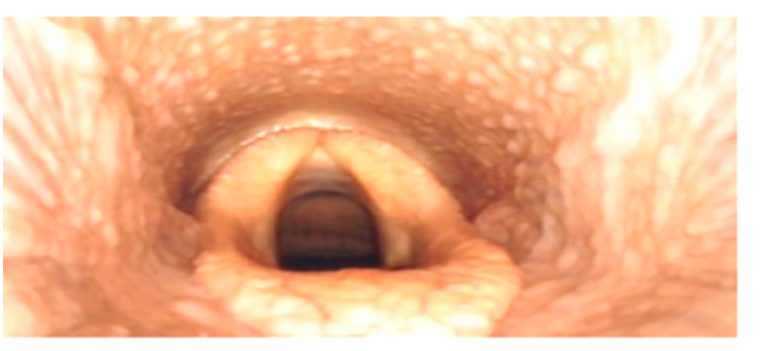

Bronchoskopie

Die Bronchoskopie, umgangssprachlich auch als Lungenspiegelung bezeichnet, wird als weiterführende Diagnosemethode bei Atemwegserkrankungen eingesetzt.

Bei der Entscheidung, zu welchem Zeitpunkt die Bronchoskopie durchgeführt werden sollte, ist die ausführliche Anamnese unverzichtbar. Ergibt der Vorbericht, dass die Erkrankung schon lange besteht und/oder dass andere Therapeuten bereits Breitbandantibiotika ohne langfristigen Erfolg eingesetzt haben, sollte unbedingt direkt eine Bronchoskopie mit bakterieller Untersuchung durchgeführt werden, um die Entstehung von Antibiotikaresistenzen nicht unnötig zu fördern und gezielt ein Antibiotikum auswählen zu können. Ansonsten findet üblicherweise zunächst ein symptomatischer Therapieversuch statt und nur wenn dieser nicht den gewünschten Erfolg erbringen kann, wird eine Bronchoskopie empfohlen. Leider sind auch in der Tiermedizin mittlerweile multiresistente Keime keine Seltenheit mehr.